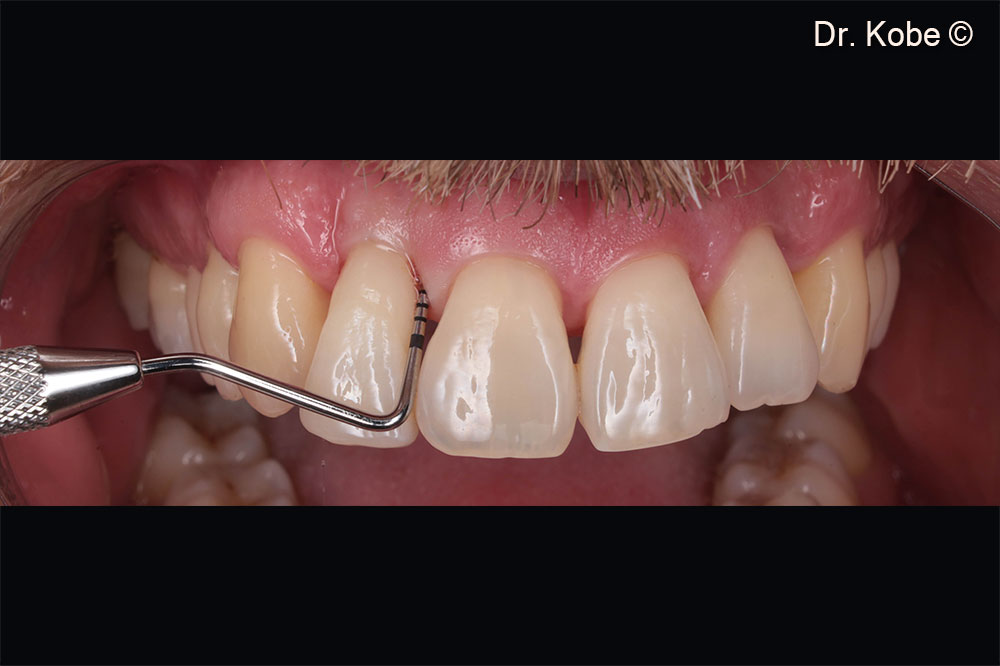

Initial situation in the second quadrant